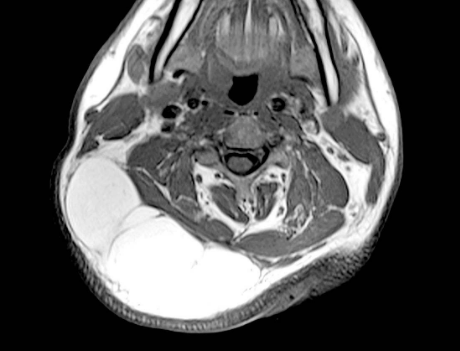

脂肪瘤圖片

脂肪瘤